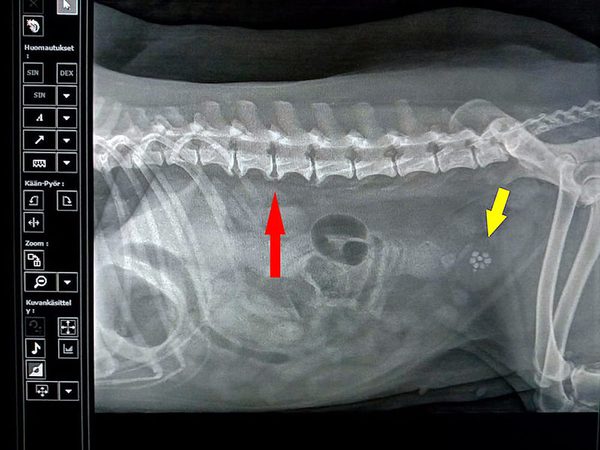

Bättre och mobil röntgenutrustning ger smidiga och heltäckande veterinärtjänster i västra Nyland.